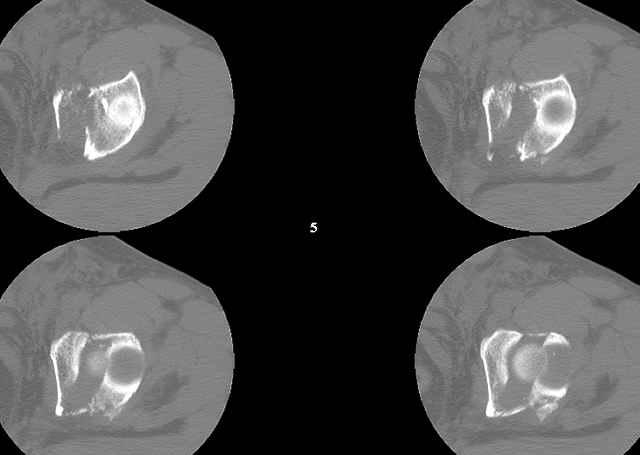

A CT scan will rarely lie to you...reveals your reduction and implants...we use it to assess, teach, grade, and try to get better next time.

Screw Fixation

-AC Screw

-PC Screw

For Alex... here are some cannulated and 7mm screws for you... notice the fracture malreduction as indicated by the head subluxation on both views...this was a percutaneous technique without open reduction... I don¹t like it but there it is... the fixation technique is not at fault, because there was no open reduction of the fracture... but let¹s not get in to all that.